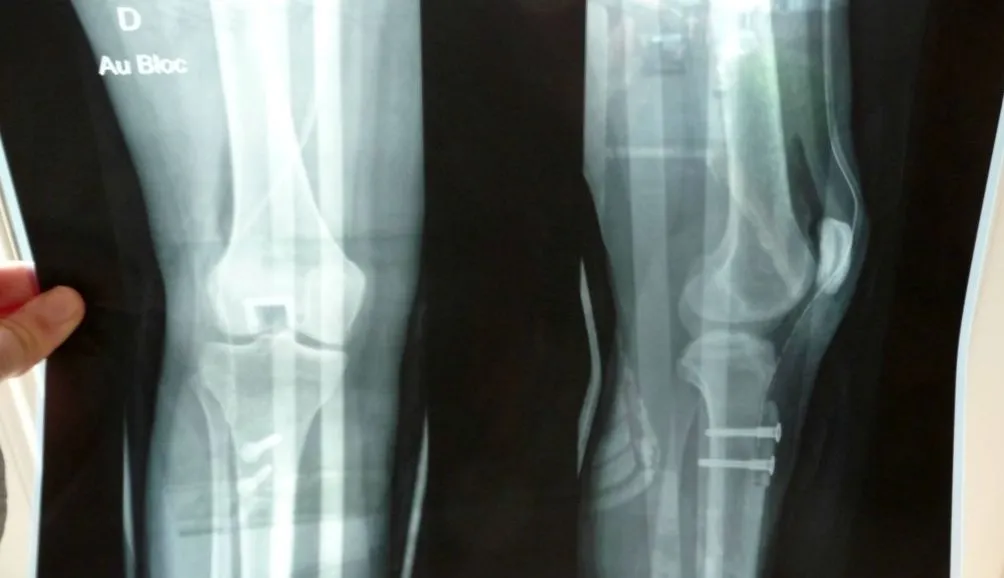

Depuis 2012, les amis de l’anatomie profitent du 8 novembre pour célébrer la journée internationale de la radiologie. Les footeux aussi.